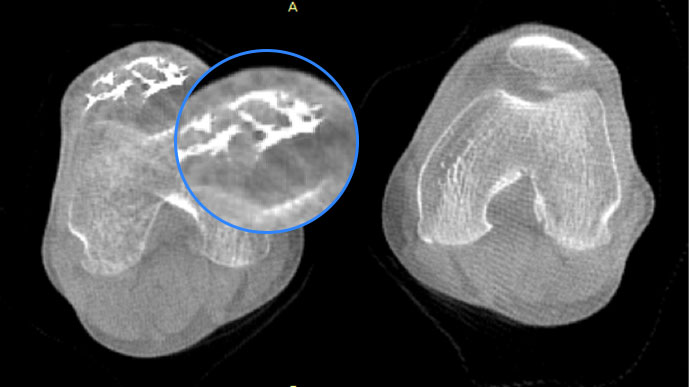

• 膝關節

智能金屬偽影抑制算法

關閉金屬偽影校正

開啟金屬偽影校正